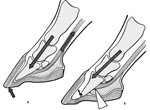

Fitting a heartbar shoe to a laminitic horse

The correct method of application of a heartbar shoe is crucial to the recovery of a laminitic animal. This should always be done with veterinary consultation.

Recent x-rays are essential to help position the shoe correctly.

The shoe is designed so that the frog carries a significant proportion of weight that would have been normally supported by the wall and sole; especially at the heels. The farriery term for this is a loaded heartbar shoe.

The bar in the shoe replicates the triangular shape of the frog, and lays flat on it within its perimeter. The tip of the bar must be perpendicular to a line drawn from the extensor process of the coffin bone within the hoof capsule The drawing pin shows the true point of the frog, giving an external reference point.

If the bar in the shoe is positioned too far forwards, the arterial blood supply to the sole will be compromised usually resulting in an abcess. If it is positioned too far back, the tip of the bone is driven downwards and can protrude through the sole.